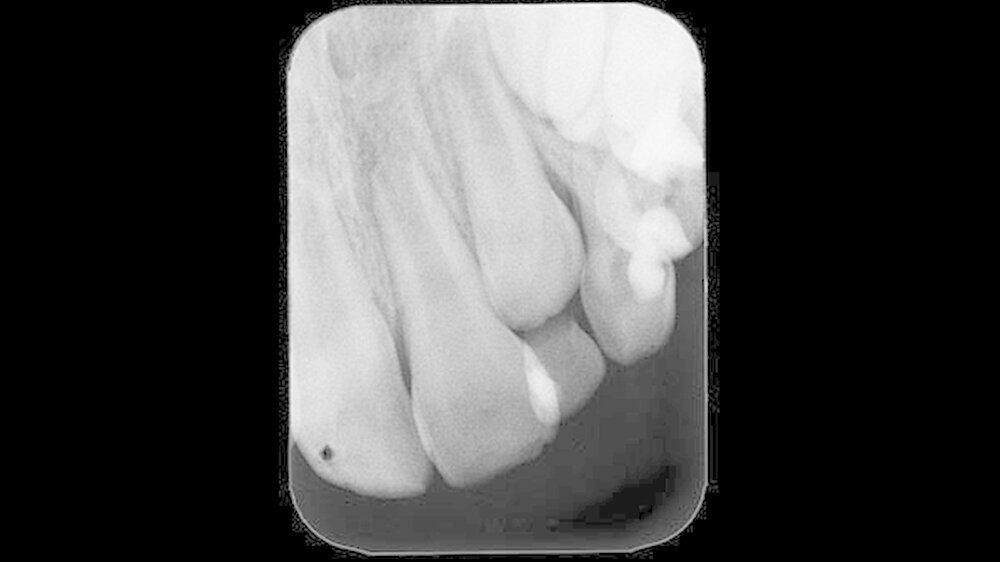

Weitere Verletzungen waren nicht vorhanden. Da sich der Unfall während eines Urlaubsaufenthalts ereignet hatte, erfolgte die Erstversorgung durch einen Zahnarzt vor Ort. Der gesunde Patient wies zu diesem Zeitpunkt ein altersentsprechendes Wechselgebiss auf. Im Zusammenhang mit der Erstversorgung wurde ein Zahnfilm (Abbildung 1) angefertigt.

Fokussiert auf den betroffenen Zahn 21 zeigte dieser ein nicht abgeschlossenes Wurzelwachstum und ließ eine unfallbedingte Schmelzabsplitterung an der Inzisalkante erkennen. Eine Wurzelfraktur am betroffenen Zahn sowie eine Alveolarknochenfraktur ließen sich auf der angefertigten Aufnahme nicht vermuten. Da es zu keinen weiteren Beschwerden und einem komplikationsfreien Verlauf kam, stellte sich der Patient zu keiner weiteren Kontrolluntersuchungen beim Zahnarzt am Heimatort vor.